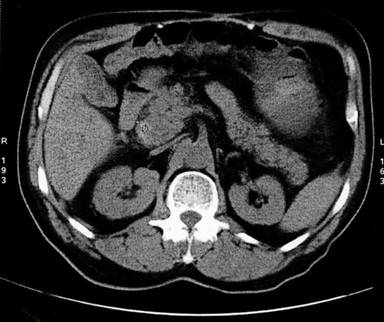

One day after admission, the occurrence of hematemesis urged repeated endoscopy, which revealed the fresh blood originating from the papilla of Vater (Figure 1). Endoscopic retrograde cholangiopancreatography was performed, demonstrating patent pancreatic duct and blind remnant of native common bile duct without communications between pancreaticobiliary tract and blood vessels. During the procedure few blood clots originated from the papilla of Vater. Multislice contrast computed tomography showed moderate enlargement of the pancreatic head with suspected hematoma (Figure 2), along with three splenic artery aneurysms, of 30 mm, 12 mm and 8 mm in diameter, in the distal arterial segment, as well as anastomotic stenosis of native and donor hepatic artery. However, contrast extravasation on visceral angiography was not detected (Figure 3). The embolization of the splenic artery aneurysms was judged unfeasible due to tortuosity of the splenic artery, wide neck of the major aneurysm and proximity of other two aneurysms to the splenic hilum. Supportive therapy stabilized the patient and gastrointestinal bleeding resolved. The patient was scheduled for surgery; however, subsequent development of hepatic artery thrombosis, resulted in multiple liver abscesses and septic episodes (Figure 4). On several occasions Enterococcus faecium and Klebsiella pneumoniae were identified from abscesses and blood cultures. Despite of a broad-spectrum antibiotic therapy and percutaneous drainage the fever persisted, although gastrointestinal bleeding did not reoccur. Three months later, the patient underwent liver re-transplantation and splenectomy. During the three past years of follow-up, the patient has remained uneventful.

Figure 2. Non-contrast abdominal CT scan showing moderate enlargement of the pancreatic head and surrounding fat edema-pancreatitis classified as Balthazar score 1. A small hyperdense lesion within pancreatic head suspected of small hematoma is notable. |